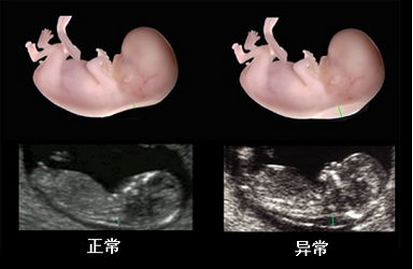

在线咨询系统彩超和四维彩超我们都不陌生,尤其是孕妇,在怀孕期间孕妈妈一定有做过类似的检查,此二者都是观察胎儿健康的检查项目,所以在产检中非常重要,那么,系统彩超和四维彩超有什么区别呢?下面就让贵阳和谐阳光产科医生为我们解答。

1.四维彩超:由于四维彩超是一种立体B超检查,所以除了能检查常规的项目之外,还可针对心肝脾肺各个脏器 及唇腭裂方面的筛查。

2.系统彩超:系统彩超早期的时候可以通过颈后透明层排除宝宝智力以及先天愚型。对胎体发育的健康状况进行比较准确的评估。

2.四维彩超:四维彩超在怀孕20——28周内做为宜。在怀孕20周后,胎儿大脑便开始迅速发育,肢体发育也已经基本完成,加上胎儿的大小和羊水比较适中,骨骼回声影响比较小,成像会比较清晰。

对胎儿全面排畸,孕妈妈除了需要做系统彩超以外,还需要做四维彩超。因为,系统彩超仅仅是对胎儿先天愚型和智力缺陷等进行排查。四维彩超是对胎儿面部、颜色等体表器官进行筛查。因此,贵阳妇产医院产科医生建议,全面排畸系统彩超和四维彩超都要做。